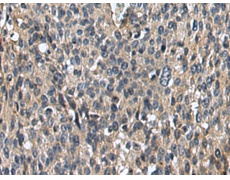

IHC positive control: |

Human ovarian cancer and Human colorectal cancer |